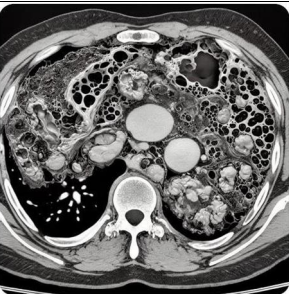

Radiological findings

Imaging Modality: CT Pelvis and Abdomen

1. Subcutaneous and Fascial Gas: Presence of gas within the subcutaneous tissues and fascial planes of the pelvic region, particularly around the lower abdomen, perineum, and pelvic floor. Air tracking along fascial planes is a hallmark of necrotizing fasciitis, strongly suggesting infection in postpartum cases.

2. Soft Tissue Edema and Thickening: Extensive thickening and increased density of subcutaneous tissues and fascial layers in the pelvic and perineal regions, with widespread edema beyond typical boundaries. This indicates rapid spread of infection, especially relevant in the postpartum period.

3. Loss of Fascial Plane Definition: Loss of normal fat plane definition between muscles and fascial layers in the pelvic region. This "fascial blurring" is characteristic of aggressive soft tissue infection.

4. Fluid Collections or Abscesses: Irregular fluid collections may be present, potentially indicating abscess formation along the pelvic fascial planes or in perineal tissues. These collections often have heterogeneous densities and may contain gas bubbles or necrotic tissue.

Figure 1